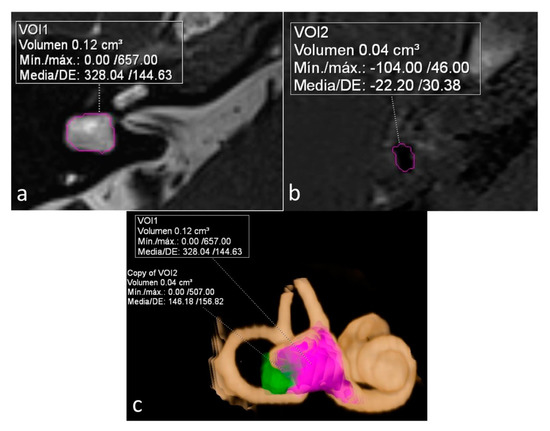

ELR ranged from 22% to 81%. It´s interesting to note that both extremes were present in the same patient, corresponding to a patient with right unilateral Ménière’s syndrome but with bilateral LSCCD (patient 4). On the dysplastic clinically affected side, ELR was 81% (Figure 2), whereas on the dysplastic clinically asymptomatic ear, ELR was barely 22% (Figure 3). In patients with unilateral LSCCD and available hydrops MR imaging (patients 3 and 5), the contralateral “normal anatomy” inner ear showed no signs of endolymphatic hydrops with endolymphatic ratios of less than 25% (not shown). The contralateral “normal anatomy” inner ear was asymptomatic.

Figure 2.

Patient with bilateral LSCCD. Right clinically affected ear. (a) Heavily T2 weighed cisternography sequence with total vestibular lymph volume. (b) 3D-IR-REAL hydrops sequence shows vestibular endolymphatic volume (dark signal). Note also cochlear hydrops. (c) Overlay of both volume values in the cisternography sequence for the calculation of the endolymphatic ratio (ELR). (d) 3D volume-rendered image of the inner ear with color coded overlay of both cisternal and vestibular hydrops volumes. ELR of 81% suggesting severe vestibular hydrops.